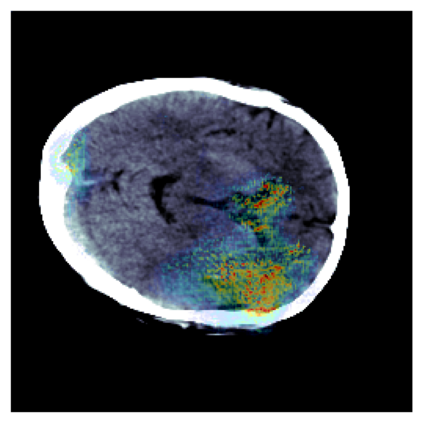

The sigmoid activation is the standard output activation function in binary classification and segmentation with neural networks. Still, there exist a variety of other potential output activation functions, which may lead to improved results in medical image segmentation. In this work, we consider how the asymptotic behavior of different output activation and loss functions affects the prediction probabilities and the corresponding segmentation errors. For cross entropy, we show that a faster rate of change of the activation function correlates with better predictions, while a slower rate of change can improve the calibration of probabilities. For dice loss, we found that the arctangent activation function is superior to the sigmoid function. Furthermore, we provide a test space for arbitrary output activation functions in the area of medical image segmentation. We tested seven activation functions in combination with three loss functions on four different medical image segmentation tasks to provide a classification of which function is best suited in this application scenario.